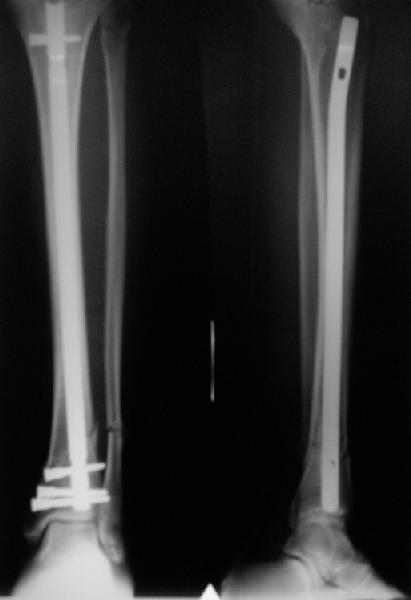

A typical case is attached, also an image with intra-op reduction obtained by a small wire distractor, in the moment of insertion a Poller wire in AP direction. Fixation by a SIGN nail. Despite the fibula was not fixed healing was obtained with the unchanged alignment.

[ Ответить ]

Very interesting application, but is the final position in a little distal varus with some fibula

distraction? Would that have been eliminated by fibula plating?

TDVC> Very interesting application, but is the final position in a

TDVC> little distal varus with some fibula distraction?

At least both the ankle mortise and tibial alignment look acceptable, don't they?